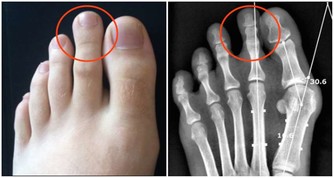

2.生理構造

曲腿、平足、下墜的腳踝、內八字,

這些天生因素加上經常受傷,

都會造成膝蓋背離生長軌道。

要知道從足到臀的聯動是高度獨立的,

如果某一部位偏離「軌道」,整個系統便會失靈。